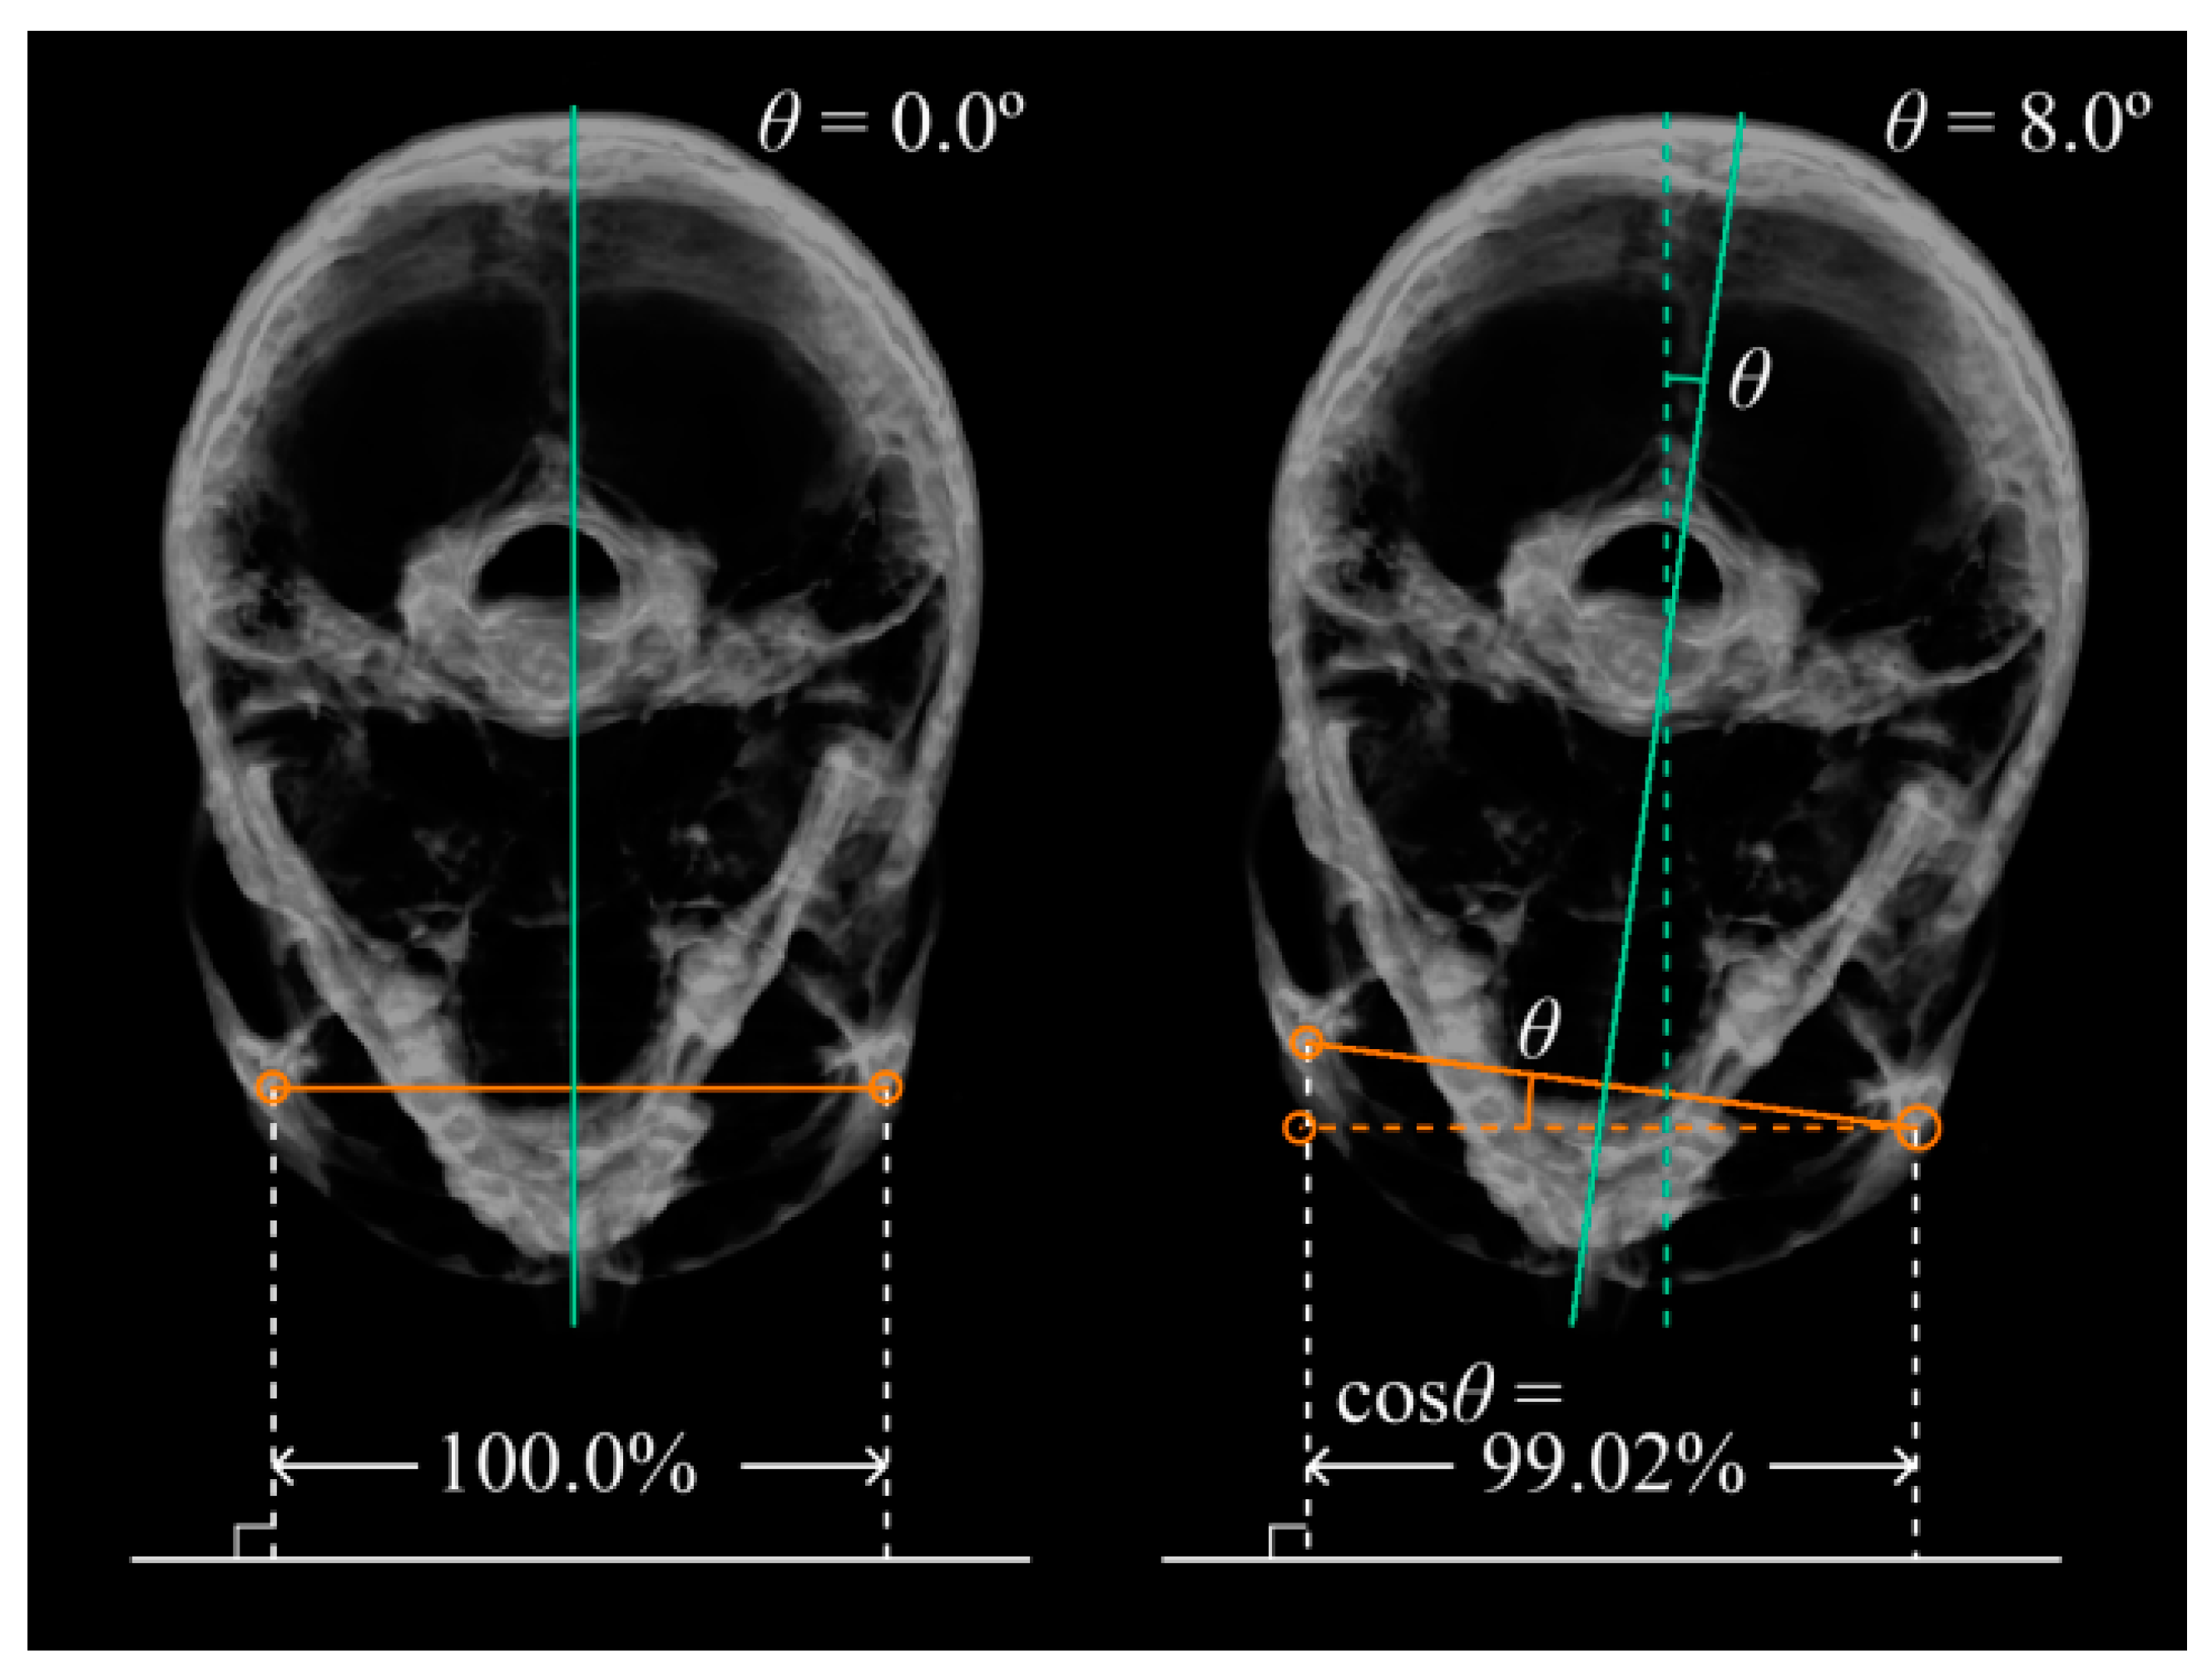

For example, it is assumed that the facial tilt of patients is characterized by front- and exact-side orientations of 0° and 90°, respectively. It is also assumed that the line connecting the left and right outermost edges of the orbits is horizontal and that its length is at its maximum when the patient is facing the front and at its minimum when the patient is facing exactly to the left side (Figure 5). If, instead, the patient is facing 8° to the left or right from the front, the measurement would be approximately 99.02% of the actual length (Figure 5 and Figure 6). In this case, if the actual length is 100 mm, the measurement would be 1 mm shorter. The error in the measurement increases rapidly as the inclinations increase.

Figure 6. Figure 4 shown using the image of the section of the patient. The image is seen from the top. The line at the bottom of the figure represents the screen plane. The left side of the figure is facing the front, and the right side is 8° facing left to the screen plane. For the correction of anterior tilt, as in the top left image of Figure 7, the line connecting the two intersections of the orbit and each orbital line is defined as the horizontal standard. For the correction of lateral tilt, as in the top right image of Figure 7, the line connecting the lowest point of the orbit and the uppermost point of the upper edge of the ear canal was defined as the horizontal standard. The setting of these reference points and the placement of the markers on the reference points are performed by the orthodontist.